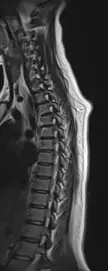

kyphosis

Neck pain MRI